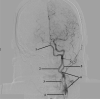

The A.N. Kazantsev artery is a vessel starting from the common carotid artery with subsequent bifurcation into 2 vessels of equal size-the internal carotid artery (ICA) and the persistent embryonic hypoglossal artery (PEHA). Until now, this artery has been considered as the ICA. However, according to all existing classifications, the ICA in the cervical segment does not have arterial branches. In addition, in view of the comparable sizes of PEHA and ICA, PEHA itself cannot be considered a branch of the ICA. Thus, by the right of the first description, the authors of the article named this vascular formation as the A.N. Kazantsev artery, which forms a bifurcation of the PEHA and ICA. In this clinical case, carotid angioplasty (CAS) was performed with stenting of 80% stenosis of the A.N. Kazantsev artery in the most acute period of acute cerebrovascular accident (ACV). According to angiography, the following was also revealed: the presence of PEHA, extending from the A.N. Kazantsev artery 5 cm above its mouth, connecting with the main artery; stenosis of the right vertebral artery 60% at the mouth; hypoplastic left vertebral artery with aplasia of the V4 segment; open circle of Willis (VC): absence of both posterior communicating arteries (PCA). Due to the high risk of recurrent CVA due to clamping of the A.N. Kazantsev artery during CEA, a multidisciplinary consultation decided to implement an emergency CAS of the A.N. Kazantsev artery. The distal embolism protection system FilterWire was inserted into the proximal part of the basilar artery through the radial artery on the left. The distal embolism protection system RX Accunet was inserted into the distal parts of the left ICA through the left common femoral artery. According to Seldinger, an Acculink stent 7-10 × 30 mm was inserted into the affected area of the A.N. Kazantsev artery, positioned and opened. The postoperative period was uneventful. ACV did not recur. Conducted dual antiplatelet therapy (acetylsalicylic acid 125 mg in the afternoon + clopidogrel 75 mg in the morning). The patient was discharged from the institution on the 10th day after the operation in a satisfactory condition.